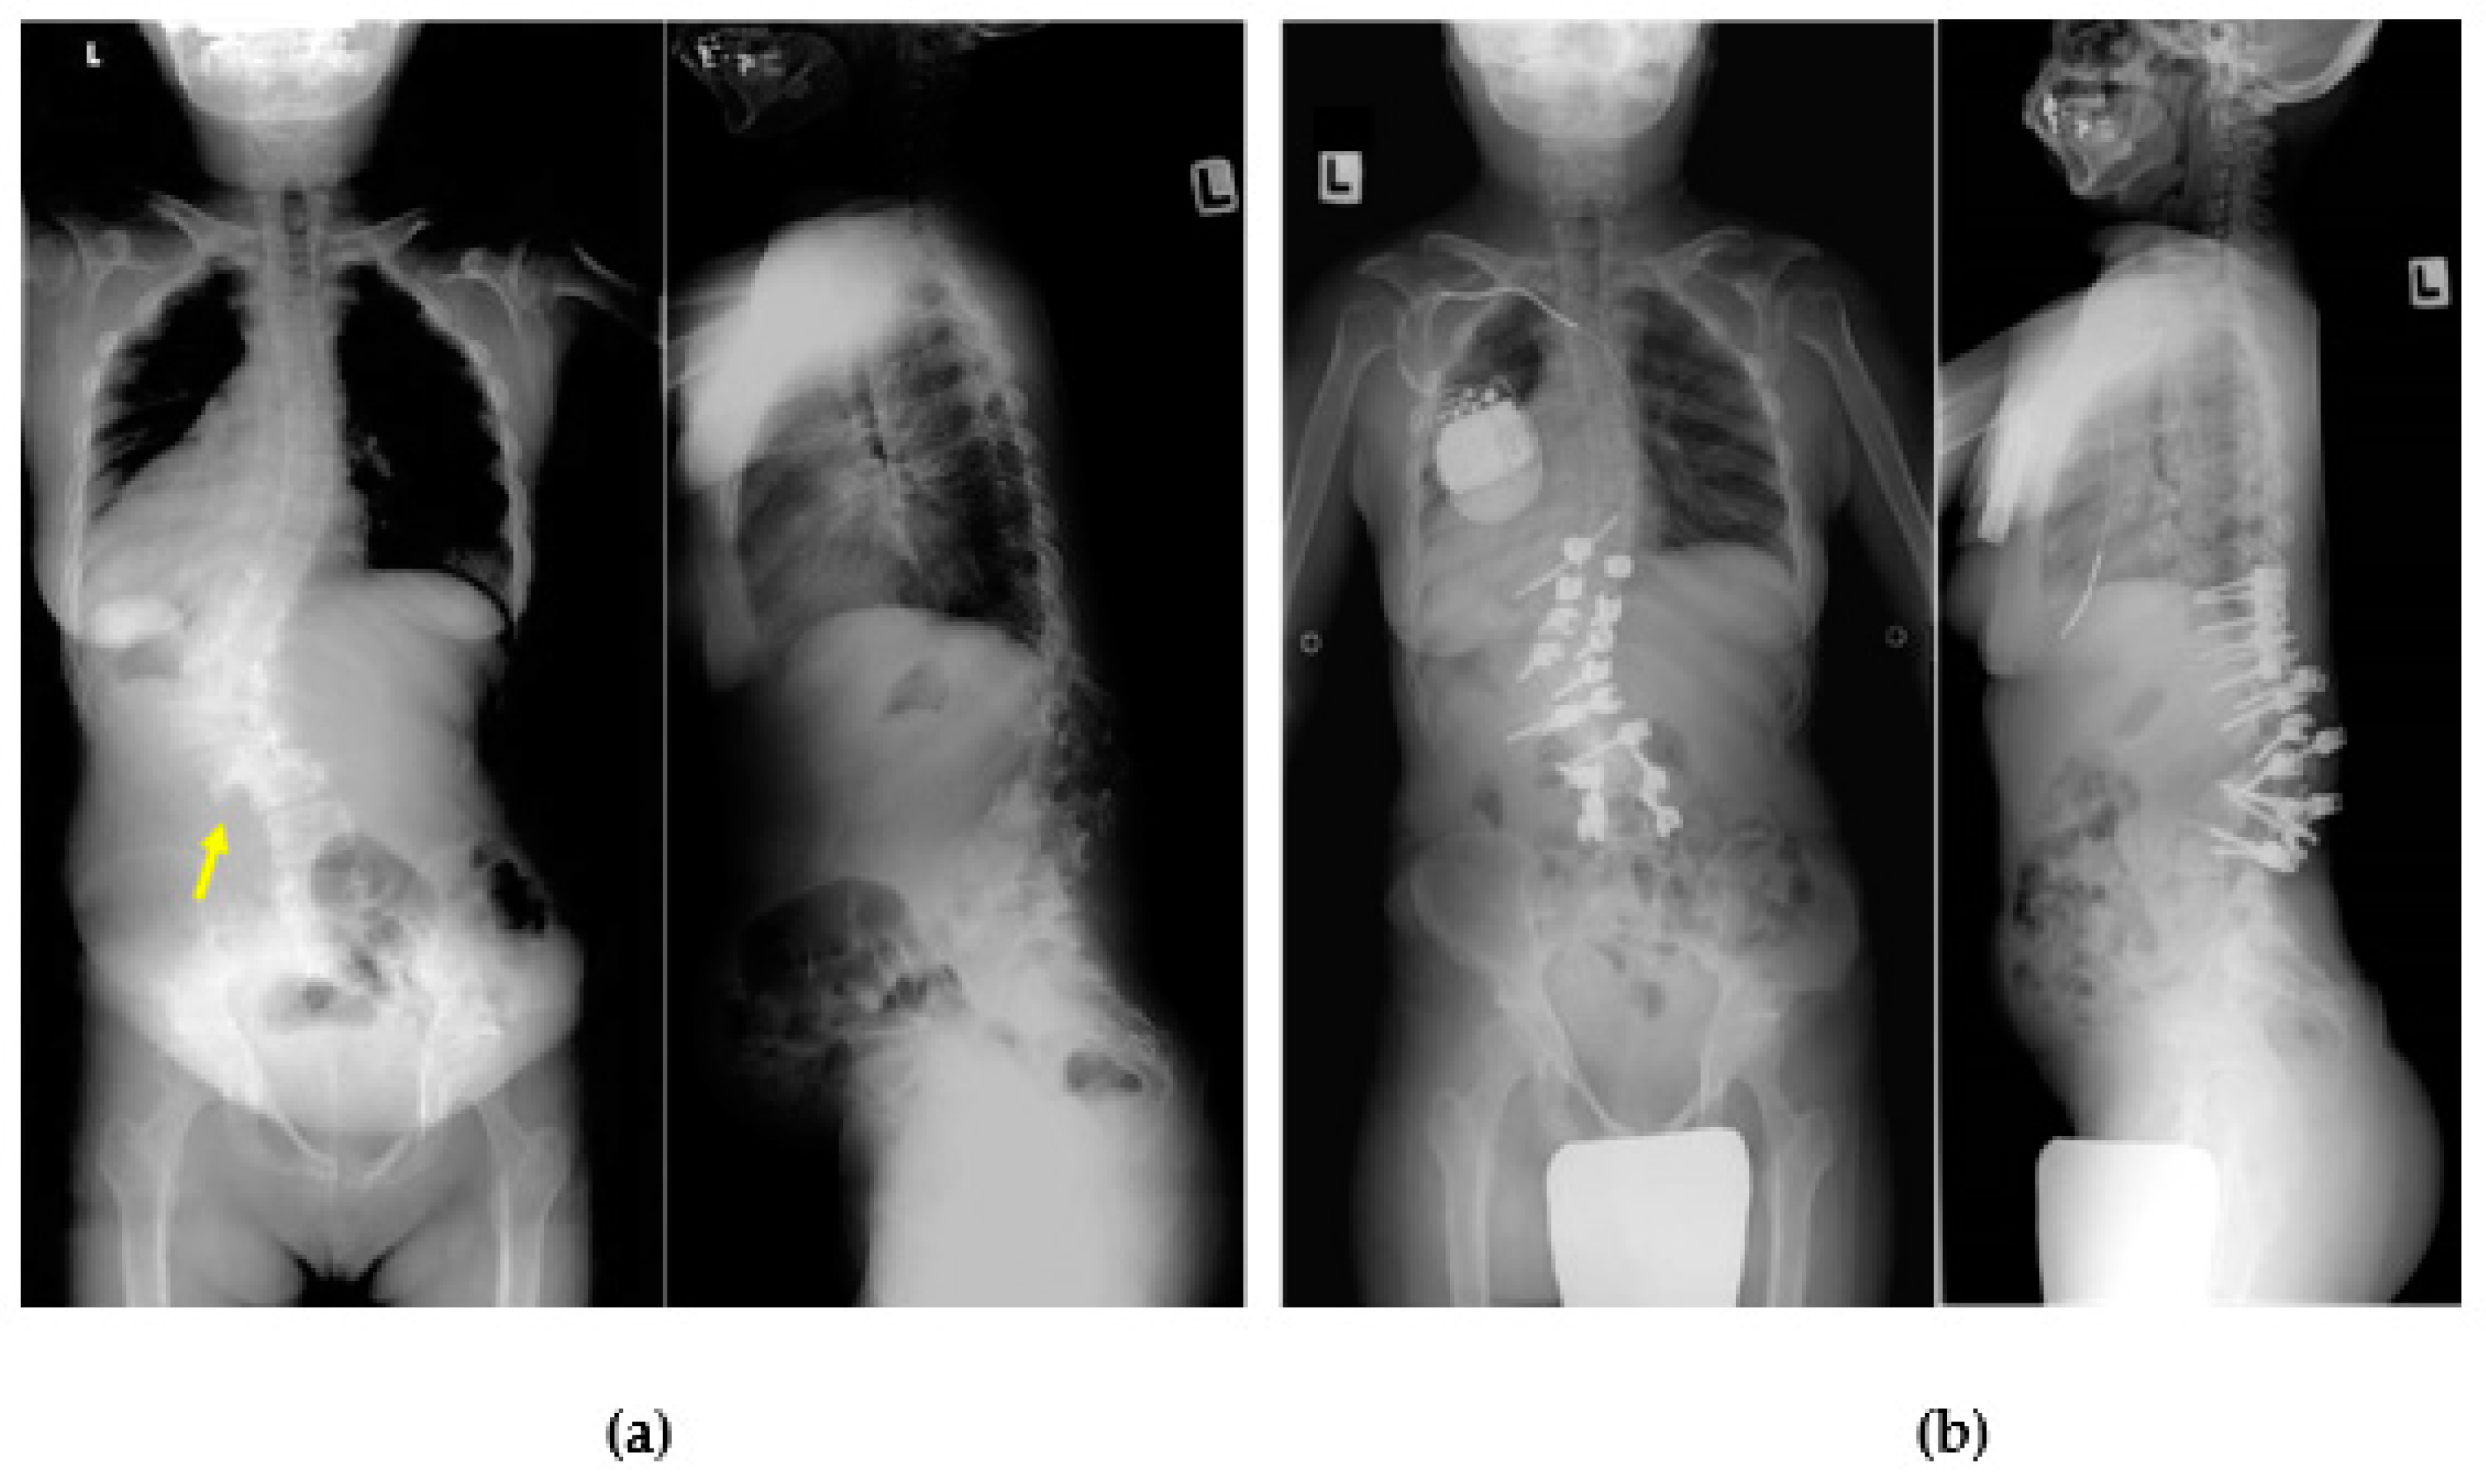

2.1.3. Thoracolumbar Kyphosis